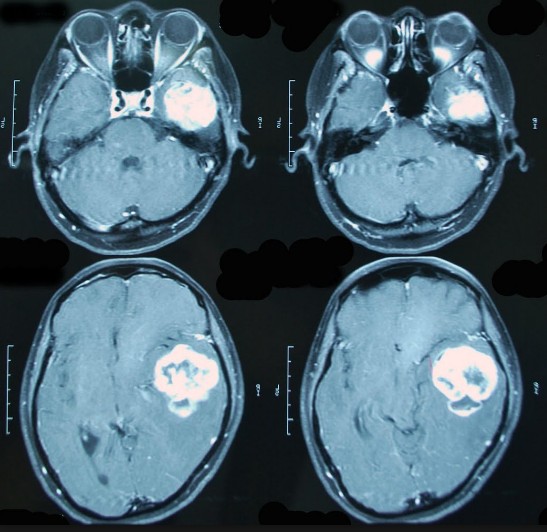

Наиболее точно и быстро поставить диагноз помогает МРТ с болюсным контрастированием – введение контрастного вещества проводят через интродюсер – внутривенный катетер, оснащенный клапаном. При болюсном томографическом обследовании улучшается обнаружение опухолей, что позволяет проводить дифференциальную диагностику для выявления здоровой и патологической тканей, для определения размеров опухоли и ее нового разрастания, а также возможных рецидивов после проведенного лечения.

Введение контраста позволяет получить более точные данные по сравнению с информацией обычной МРТ в случаях воспалительных, опухолевых и демиелинизирующих заболеваний.

При подозрении на онкологический процесс рекомендуют делать МРТ мягких тканей и органов с контрастным усилением, так как иные методы не позволяют выявить наличие и характер новообразования и метастазов. Благодаря подобным обследованиям визуализируются опухоли, сразу же после расшифровки результатов можно точно определить этиологию процесса, состояние лимфосистемы и стенок сосудов, антисклеротические наслоения.